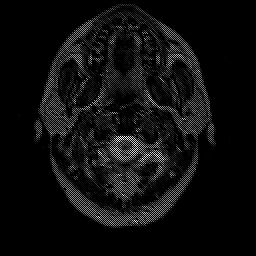

Glioma overlay -- Slice #0

[Home][Help][Clinical] Slice 0